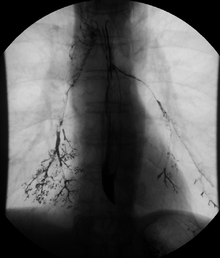

Enteroclysis

For small bowel examinations, in addition to fasting for 8 hours prior to examination, a laxative may also be necessary for bowel preparation and cleansing.[10] Enteroclysis involves the continued infusion of 500 to 1000 mL of thin barium sulfate suspension into the intestine through a duodenal tube. Then methylcellulose is instilled through the tube. Barium and methylcellulose fill the intestinal loops which can be viewed continuously using fluoroscopy, or viewed as standard radiographs taken at frequent intervals. The technique is a double-contrast procedure that allows detailed imaging of the entire small intestine. However, the procedure may take 6 hours or longer to complete and is quite uncomfortable to undergo.[13]

- Enteroclysis has shown to be very accurate in diagnosing small bowel diseases, with a sensitivity of 93.1% and specificity of 96.9%. It permits detection of lesion which may not be seen with other imaging techniques.[7] There is no significant difference in terms of detection of clinically significant findings, sensitivity or specificity between enteroclysis and CT enterography.[1] Enteroclysis compares favorably with wireless capsule endoscopy and double-balloon endoscopy in the diagnosis of mucosal abnormalities of the small bowel.[14]